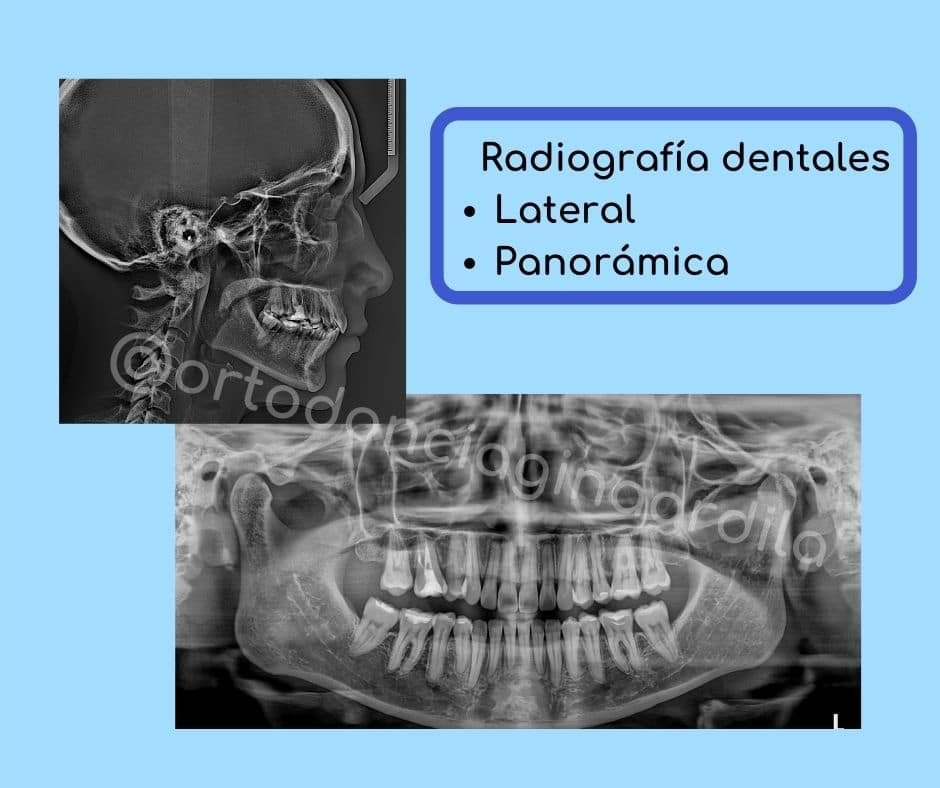

Radiografías dentales

Las radiografías dentales son los estudios más antiguos y convencionales que solicitamos los odontólogos. Allí vemos todos los dientes, los huesos, los tejidos circundantes del diente y podemos encontrar anomalías, es decir, cosas extrañas.

También contamos con las radiografías extraoral, por fuera de la boca, como son: las panorámicas (podemos ver todos los dientes de la boca y los huesos), de perfil (se ve la cabeza de medio lado, incluído los huesos del cráneo, la mandíbula, los dientes, hasta las vértebras).